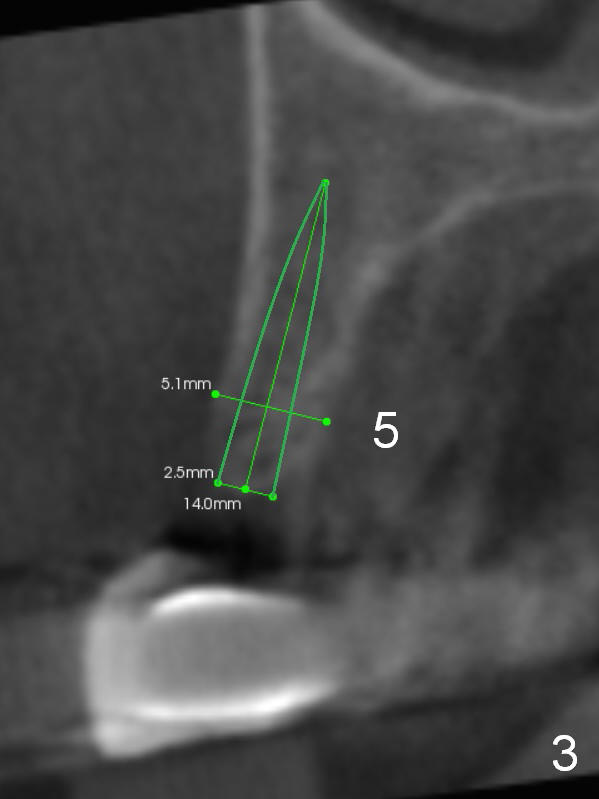

CT scan taken 10 days post immediate implant placement at #3, 4, and 10 shows that the edentulous area is narrow (Fig.1 (axial section), 2-6 (coronal sections; B: buccal)). In addition, the bone density is 100-200 Hounsfield units (Fig.2). Osteotomy should be underprep: 1.2 mm to the depth; 1.5 mm haft the depth. It appears that 2.5 or 3.0 mm 1-piece implants can be placed at #5,7 and 8 (Fig.3,5,6). Check buccopalatal trajectory after each step of osteotomy using surgical stent. Insert a 3 mm dummy implant tentatively. If it looks too wide for the ridge, use a 2.5 mm implant. If trajectory is off, use an angled one, especially at #7 (Fig.5).